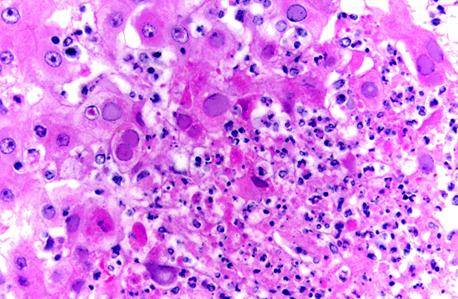

Abscess —> Well demarcated accumulations of neutrophils and/or necrotic debris

Cellulitis —> Poorly demarcated extensive neutrophilic to pyogranulomatous dermal and subcut inflam